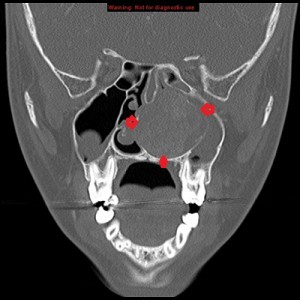

Second panel, left to right: The same set of images as in the first panel, but in bone window, showing bowing of the medial wall of the left maxillary sinus and opacified maxillary sinuses. There is no bone destruction or invasion.

Third panel, left to right: The first 2 images are coronal sections of the face showing the mass-effect of the left nasal mass on other surrounding structure.The third image in this panel is a sagittal paramedian section showing obstruction of the nasopharynx by a soft-tissue mass.